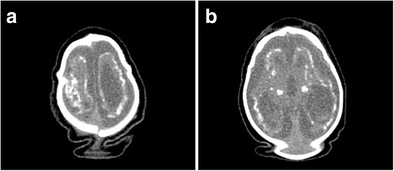

a Overriding of the cranial bones, cerebral atrophy, and anarchic distributed coarse calcifications; the excess skin as a result of the decrease in skull volume. b CT scan with gross calcifications in the basal ganglia and subcortical cortical transition